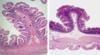

Inset: cross section of the esophagus at low magnification. At this low magnification, muscularis mucosae is barely visible under the lining epithelium. The rectangular area is examined at higher magnification to reveal the mucosa which consists of epithelium (EP). Lamina propria (LP), and muscularis mucosae (MM). Submucosa (SM) appears under the mucosa.